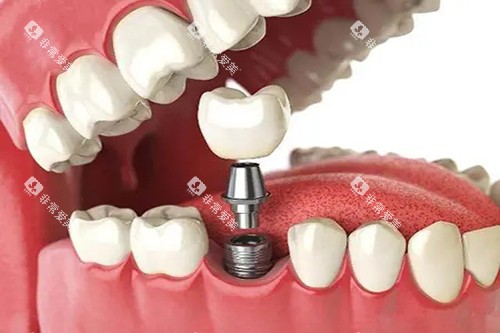

在种牙方面,医院引进了国内外可靠的种植系统,如瑞典诺贝尔种植系统、德国费亚丹种植系统等。

这些种植系统具有稳定性高、生物相容性好等特点,能够为患者提供更优质的种植体验。

在进行种植牙手术前,医生会运用可靠的口腔 CT 设备对患者的口腔状况进行齐全检查,制定个性化的种植方案。

例如,对于一些牙槽骨条件较差的患者,医生会采用骨增量技术,为种植体提供良好的支撑,提高种植可行性。